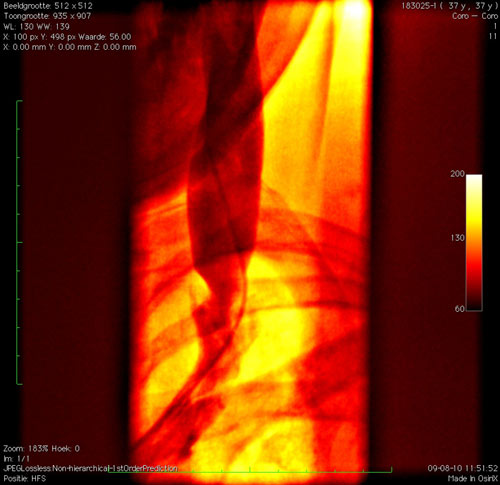

Maargoed, toen hij vertelde dat hij het eerste probleem te pakken had kon ik weer mee kijken . . . (Ik heb wat beelden toegevoegd)

Eerst heeft hij op 14 atm. een ballon van 10 mm. opgeblazen in de linker halsader maar op de PTA was er een resterende stenose zichtbaar.

Zo werd met een 12 mm ballon en een werkdruk van maximaal 6 atm andere PTA uitgevoerd en de doorstroom nam aanzienlijk toe na de tweede dilatatie.

Opmerkingen bij bestand: Voor de behandeling

Bastiaan1.jpg

Bastiaan1.jpg [ 49.04 KiB | 97086 keer bekeken ]

Opmerkingen bij bestand: Na 1e behandeling

Bastiaan2.jpg

Bastiaan2.jpg [ 42.03 KiB | 97086 keer bekeken ]

Opmerkingen bij bestand: Na 2e behandeling

Bastiaan3.jpg

Bastiaan3.jpg [ 49.69 KiB | 97086 keer bekeken ]